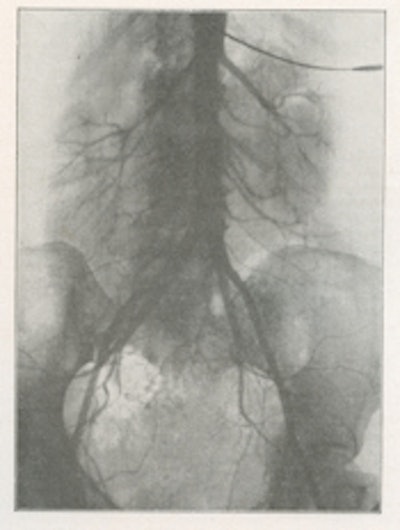

In 1929, Moniz's surgical colleague Reynaldo dos Santos, a professor of surgery in Lisbon, introduced percutaneous translumbar aortography (TLA) by direct aortic puncture with injection of a sodium iodide solution. Three years later, Santos described the technique (figs. 5 and 6). Fig. 7 shows abnormal vascularity in a sigmoid tumor; note the stationary grid lines.

Fig. 7: Translumbar aortography for sigmoid tumor shows abnormal vascularity (1932).